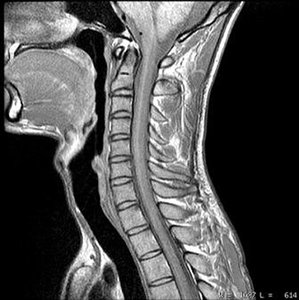

FIG 1 Sagittal MRI Normal

I often review films after a patient has been in a car accident and is experiencing persistent neck pain and other symptoms. An MRI was ordered and shows nothing of significance; in fact, the report reads that there is no evidence of trauma or pathology: normal study. If the case ultimately goes to litigation, as can sometimes occur, it becomes an issue as to why a cervical X-ray series was recommended and performed if the MRI study was normal. It becomes even more complicated if the X-rays demonstrate intersegmental ligamentous instability in the flexion and extension views. Too often the MRI is used to rule out ligamentous injury, which it often will not demonstrate because the small ligamentous structures that stabilize the cervical segments are not well-demonstrated. Often only the stress of active weight-bearing motion will demonstrate the instability. Chiropractors and physicians who specialize in musculoskeletal disorders know this, but not all health care practitioners do.

Case in point: A patient experienced ongoing pain in the neck radiating into the traps with intermittent headaches as a result of a whiplash injury from an auto accident eight months ago. The MRI was normal, as was the cervical spine study, except for intersegmental instability at the C3-4 motor unit, which indicates biomechanical hypermobility. This finding was not demonstrated on the MRI. (Figures 1-3)